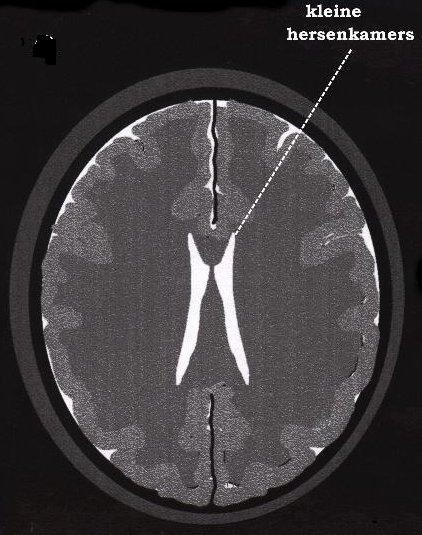

Pseudotumor cerebri (Hipertensiunea intracraniana idiopatica)